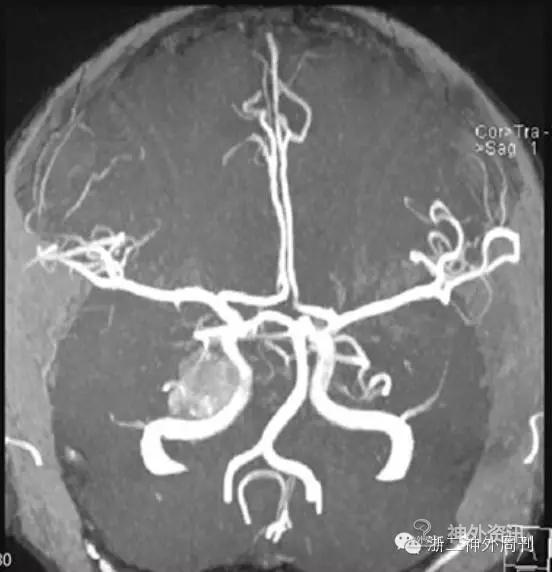

MRA示:右侧中后颅窝肿块伴出血,推移右侧颈内动脉海绵窦段,邻近右侧后交通动脉、右侧大脑后动脉、小脑上动脉,轻度受压推移(图2)。

图2. 右侧中后颅窝肿瘤出血。